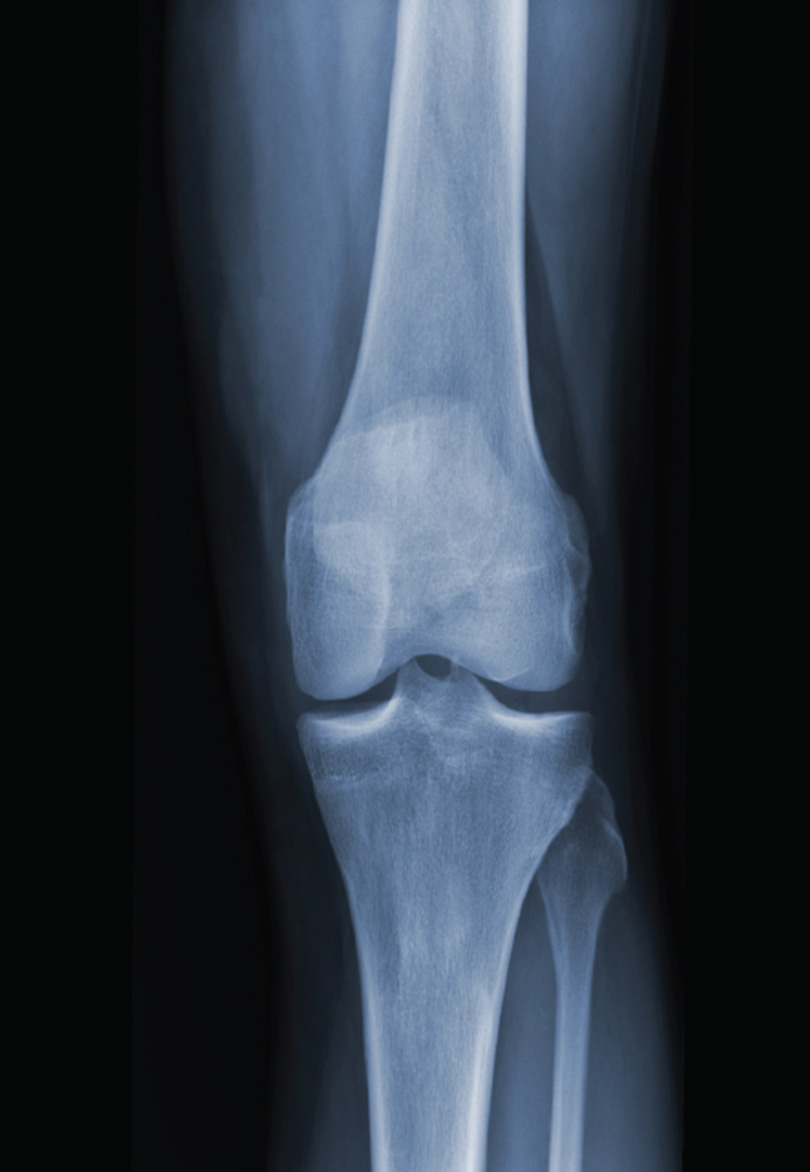

X-Ray

Musculoskeletal

Ultrasound